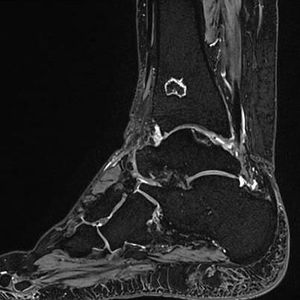

A binomial (or composite) excitation pulse is used, which achieves minimum excitation of fat protons and maximum excitation of water protons. Thus, the fat protons will not contribute to the MR signal. Fig. Sagittal three-dimensional double-echo steady-state (3D DESS) MR image of the ankle with Water Excitation (WE). Water excitation technique provides high SNR and resolution with robust fat suppression within reasonable acquisition times. This technique is mainly used for cartilage imaging. Image dataset acquired at 3.0 Tesla. Image courtesy of Bac Nguyen.